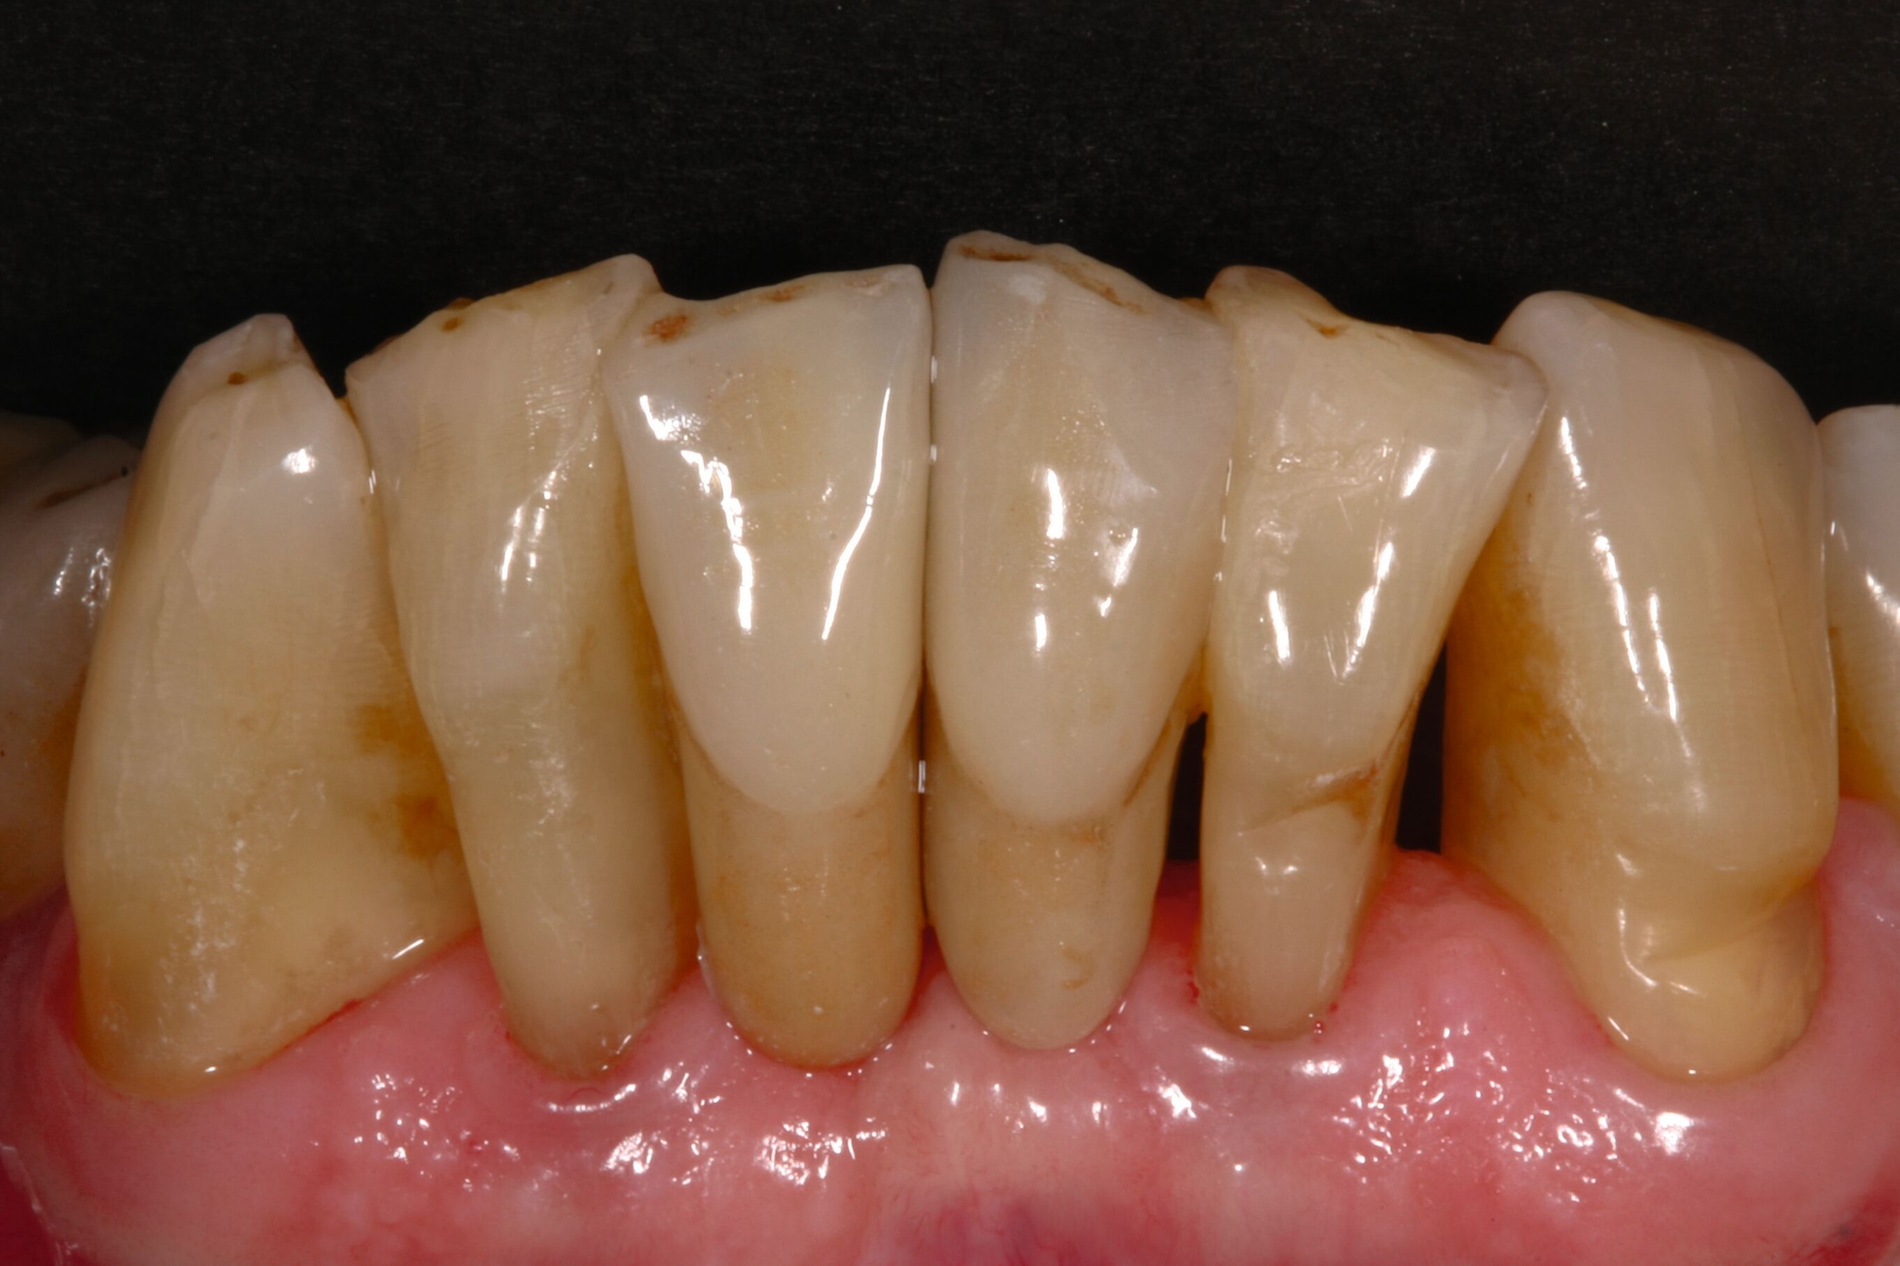

Der Patient wies verkürzte Zahnreihen im Ober- und im Unterkiefer sowie zusätzliche Schaltlücken im Unterkiefer auf (Abbildung 9). Nach Abschluss der ersten beiden Stufen der Therapie (nicht-chirurgische Parodontitistherapie), die darauf abzielte, alle vorhandenen Zähne zu erhalten, wurden an allen Zähnen Sondierungstiefen von maximal vier Millimetern erreicht. Anschließend erfolgte die Planung des definitiven Zahnersatzes im Sinne der aktuellen Leitlinien-Empfehlungen:

Ein Ersatz der Molaren war nicht erforderlich, da der Patient mit der verkürzten Zahnreihe seine Kaufunktion als ausreichend empfand. Aufgrund der erhöhten Beweglichkeit der Oberkieferfrontzähne, die die mundgesundheitsbezogene Lebensqualität stark beeinträchtigte, wurde eine adhäsive Schienung von Zahn 13 bis 21 durchgeführt. Dabei kam ein Polyethylen-Fasernetz (Ribbond, Seattle, USA) zum Einsatz (Abbildung 10). Zur Versorgung der Freiendsituation wurden zwei Implantate mit lokalem Knochenaufbau inseriert und mit implantatverankerten zementierten Einzelkronen versorgt. Die Frontzahnschaltlücke im Unterkiefer wurde mit zwei einflügeligen Adhäsivbrücken aus labial verblendeter 3Y-TZP-Zirkonoxidkeramik (Abbildungen 11 bis 13) geschlossen, die Schaltlücken regio 44 und 46 durch eine Anhängerbrücke, die von Zahn 47 bis Zahn 44 reichte (Abbildung 14).

Der Patient konnte über einen Zeitraum von mehr als 20 Jahren nachbeobachtet werden. In den ersten 14 Jahren stellte er sich jährlich in der Klinik zur unterstützenden Parodontitistherapie und Kontrolle der Restaurationen vor (Abbildung 15). Der parodontale Zustand konnte stabil gehalten werden und auch die prothetischen Versorgungen erwiesen sich komplikationsfrei.

Danach wurde der Klinikbesuch für den inzwischen 83-Jährigen zu beschwerlich, und er wurde von einem wohnortnahen Zahnarzt betreut. Die von ihm 19 Jahre nach Eingliederung des Zahnersatzes angefertigte Panoramaschichtaufnahme dokumentiert die unveränderte prothetische Versorgung des Unterkiefers sowie die stabile Situation der verkürzten Zahnreihe im Oberkiefer (Abbildung 16). Für eine detaillierte Darstellung des Fallberichts wird auf die Originalpublikation verwiesen [Wolfart und Kern, 2024].